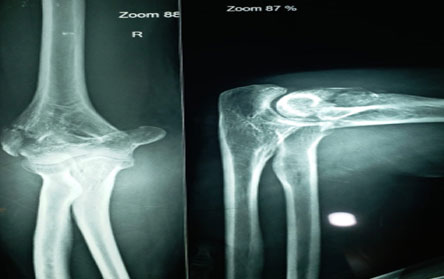

Trauma surgery:

Trauma surgery is a surgical specialty that utilizes both operative and non-operative management to treat traumatic injuries.

The Center of Orthopedics KUMAR ORTHO HOSPITAL ,Patna, offers the entire spectrum of modern orthopedic management, which is effective, patient - friendly & result oriented. In a nutshell, it is one stop treatment for all orthopedic ailments and fractures with emphasis on avoidance of complications, rapid mobilization, decreased period of confinement and an early return to normalcy.